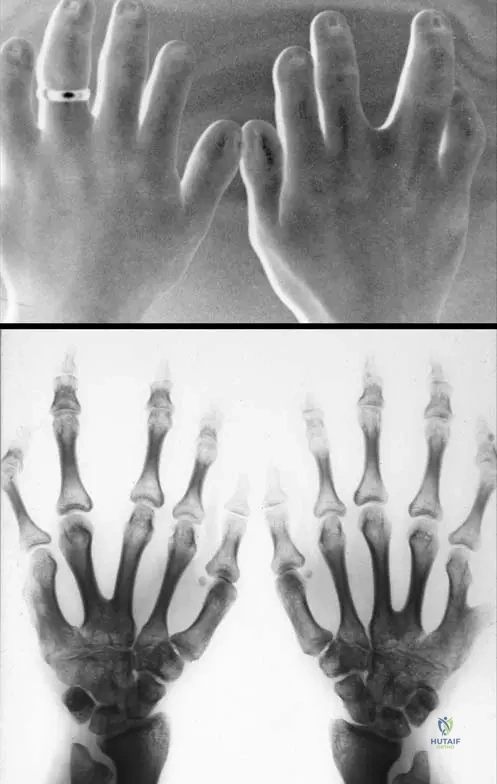

This module contains 50 advanced orthopedic multiple-choice questions meticulously developed to mirror the Arab Board of Orthopedic Surgery examinations. These questions are derived from the clinical teaching case: 1.2.3 Chondroectodermal Dysplasia (Ellis–Van Creveld’s Syndrome).